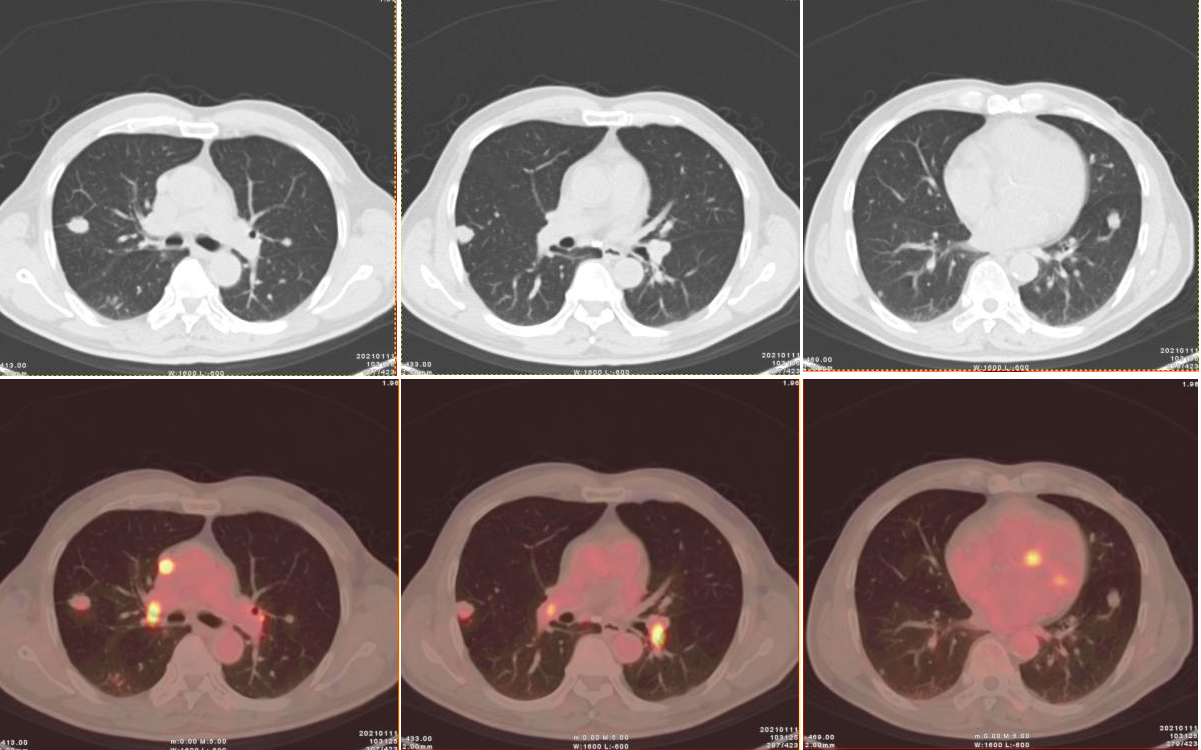

圖2、3:(上為CT橫斷位圖像,下為橫斷位融合圖像):雙肺多發(fā)結(jié)節(jié),部分可見淺分葉,邊緣可見段毛刺,代謝輕度增高。

雙肺見多發(fā)散在大小不一實性結(jié)節(jié),邊界尚清,形態(tài)不規(guī)則,部分邊緣見短棘突及淺分葉,密度不等,CT 值約19~30Hu,大者位于右肺下葉背段,大小約 1.7×1.8×2.1cm;部分病灶放射性攝取輕度增高,早期 SUVmax 3.47,1小時延時顯像示病灶放射性攝取有所減低,SUVmax 2.1。

PACC為低度惡性腫瘤,較常見的肺癌 (如鱗狀細(xì)胞癌)預(yù)后好,但在CT上,PACC無明顯特異性表現(xiàn),與常見的肺癌類型無法鑒別。本例中雙肺十幾個結(jié)節(jié)中部分病灶呈現(xiàn)放射性攝取輕度增高,早期SUVmax 3.47,1小時延時顯像示病灶放射性攝取有所減低,SUVmax 2.1,與其低度惡性的病理類型一致。